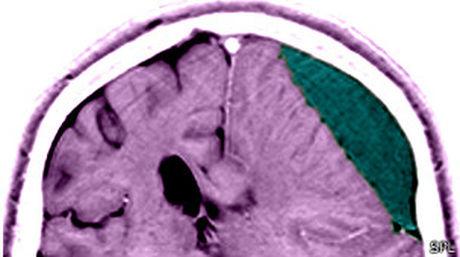

BBC Mundo / Las lesiones en la cabeza pueden dejar a las víctimas susceptibles a una muerte temprana, incluso años después, a causa de déficits de razonamiento. Esta es la ...